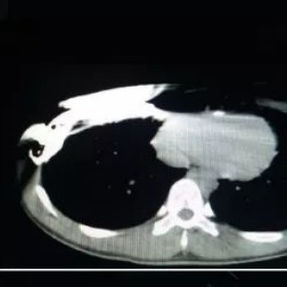

Preoperative Examination

The patient’s anterior chest wall exhibits a prominent depression deformity,characterized by a horizontal groove that affects both sides of the anterior chest wall. There is a surgical scar along the midline and one on the left side, with two scars visible on the right side of the chest wall. A 4x4 cm mass is located on the left chest wall, characterized by darkened skin and noticeable fluctuation upon palpation. The mass extends deep into the intercostal space. Mild scoliosis is also observed. The patient was ultimately diagnosed with grooved chest.

2. Improper bar Placement and Positioning: Preoperative imaging reveals that the bar was positioned along the upper edge of the groove-like depression and was placed at an angle.For optimal support and effective correction of the depressed bony structure, the bar should have been positioned at the base of the depression.